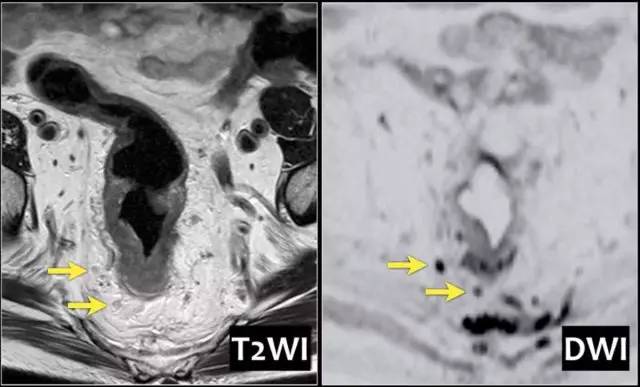

精确的淋巴结分期是重要的,因为转移淋巴结的数量影响预后。在 MRI 图像上确定淋巴结受累,传统上依赖于尺寸评估。然而反应性和转移性淋巴结之间,在尺寸上存在相当大的重叠。此外,正常大小的淋巴结中常见微转移。因此不提倡用大小来评估淋巴结是否存在肿瘤。

基于形状、边界和信号强度的标准已经被证明是更可靠的。使用这些标准,与组织病理学评估相比,MRI 确定淋巴结受累的准确度为 85%。然而阴性 MRI 成像不能排除淋巴结转移,因为成像技术不能确定淋巴结内的微转移。

以下是淋巴结分期诊断线索:

1. 均匀的淋巴结小于 10 mm,具有均匀信号强度不可疑。

2. 具有不规则边界和/或混合信号强度是可疑的。

3. 存在 1~3 个可疑淋巴结是 N1,存在 4 个或更多个是 N2。

4. 必须报告位于 CRM 1 mm 以内的任何淋巴结,因为它高度可疑 CRM 阳性。

5. 记录任何可疑骨盆侧壁淋巴结的位置和大小,这将改变放射治疗靶区。其次,外科医生将需要进行扩大淋巴结切除术(髂内淋巴结清扫)。

图 25 DWI 有助于检测淋巴结